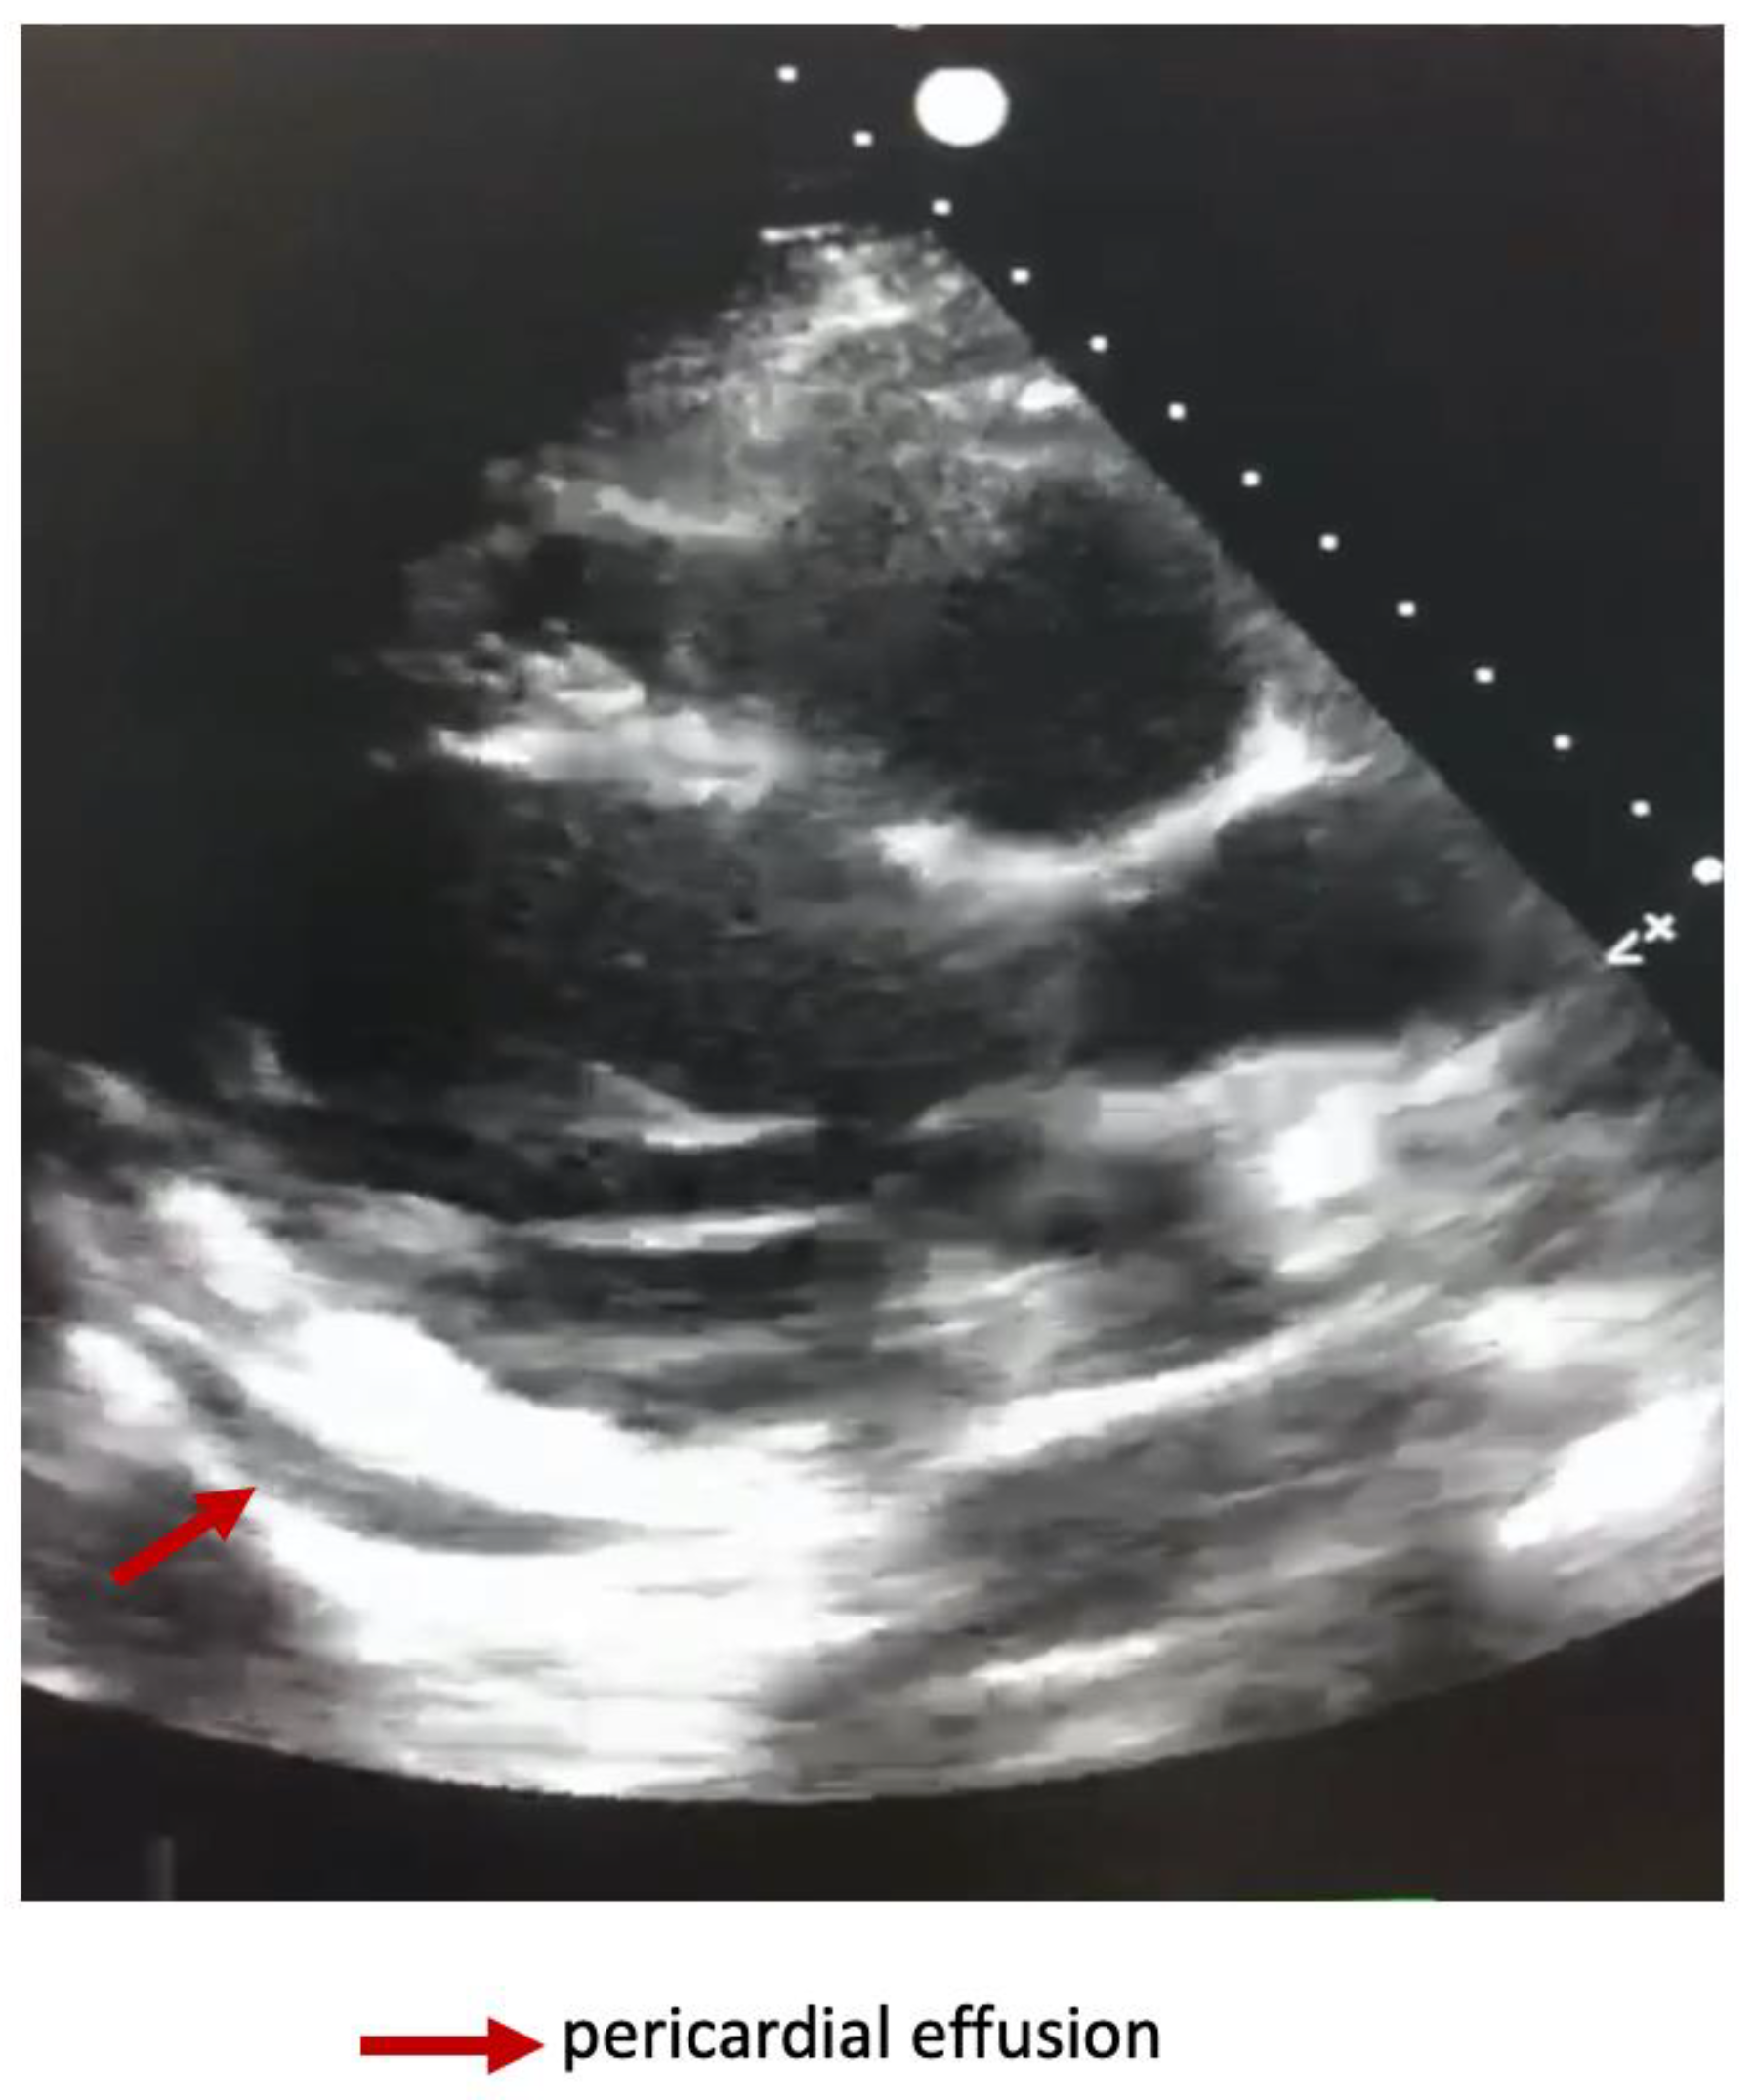

Dynamically performed cardiac ultrasound noted an improvement in the LVEF at 45-50% and minimal pericardial effusion (Figure 3).

Figure 3. Transthoracic heart ultrasound showing pericardial effusion.